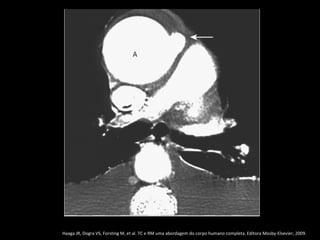

Ectasia anuloaórtica

Caracterizada pela dilatação do seio de Valsalva

com distorção da junção sinotubular que assume

configuração em forma de pera;

Causas: MARFAN, homocistinúria, Ehlers-Danlos e

osteogênese imperfeita;

Idiopática em 1/3 dos casos;

Haaga JR, Dogra VS, Forsting M, et al. TC e RM uma abordagem do corpo humano completa. Editora Mosby-Elsevier, 2009.